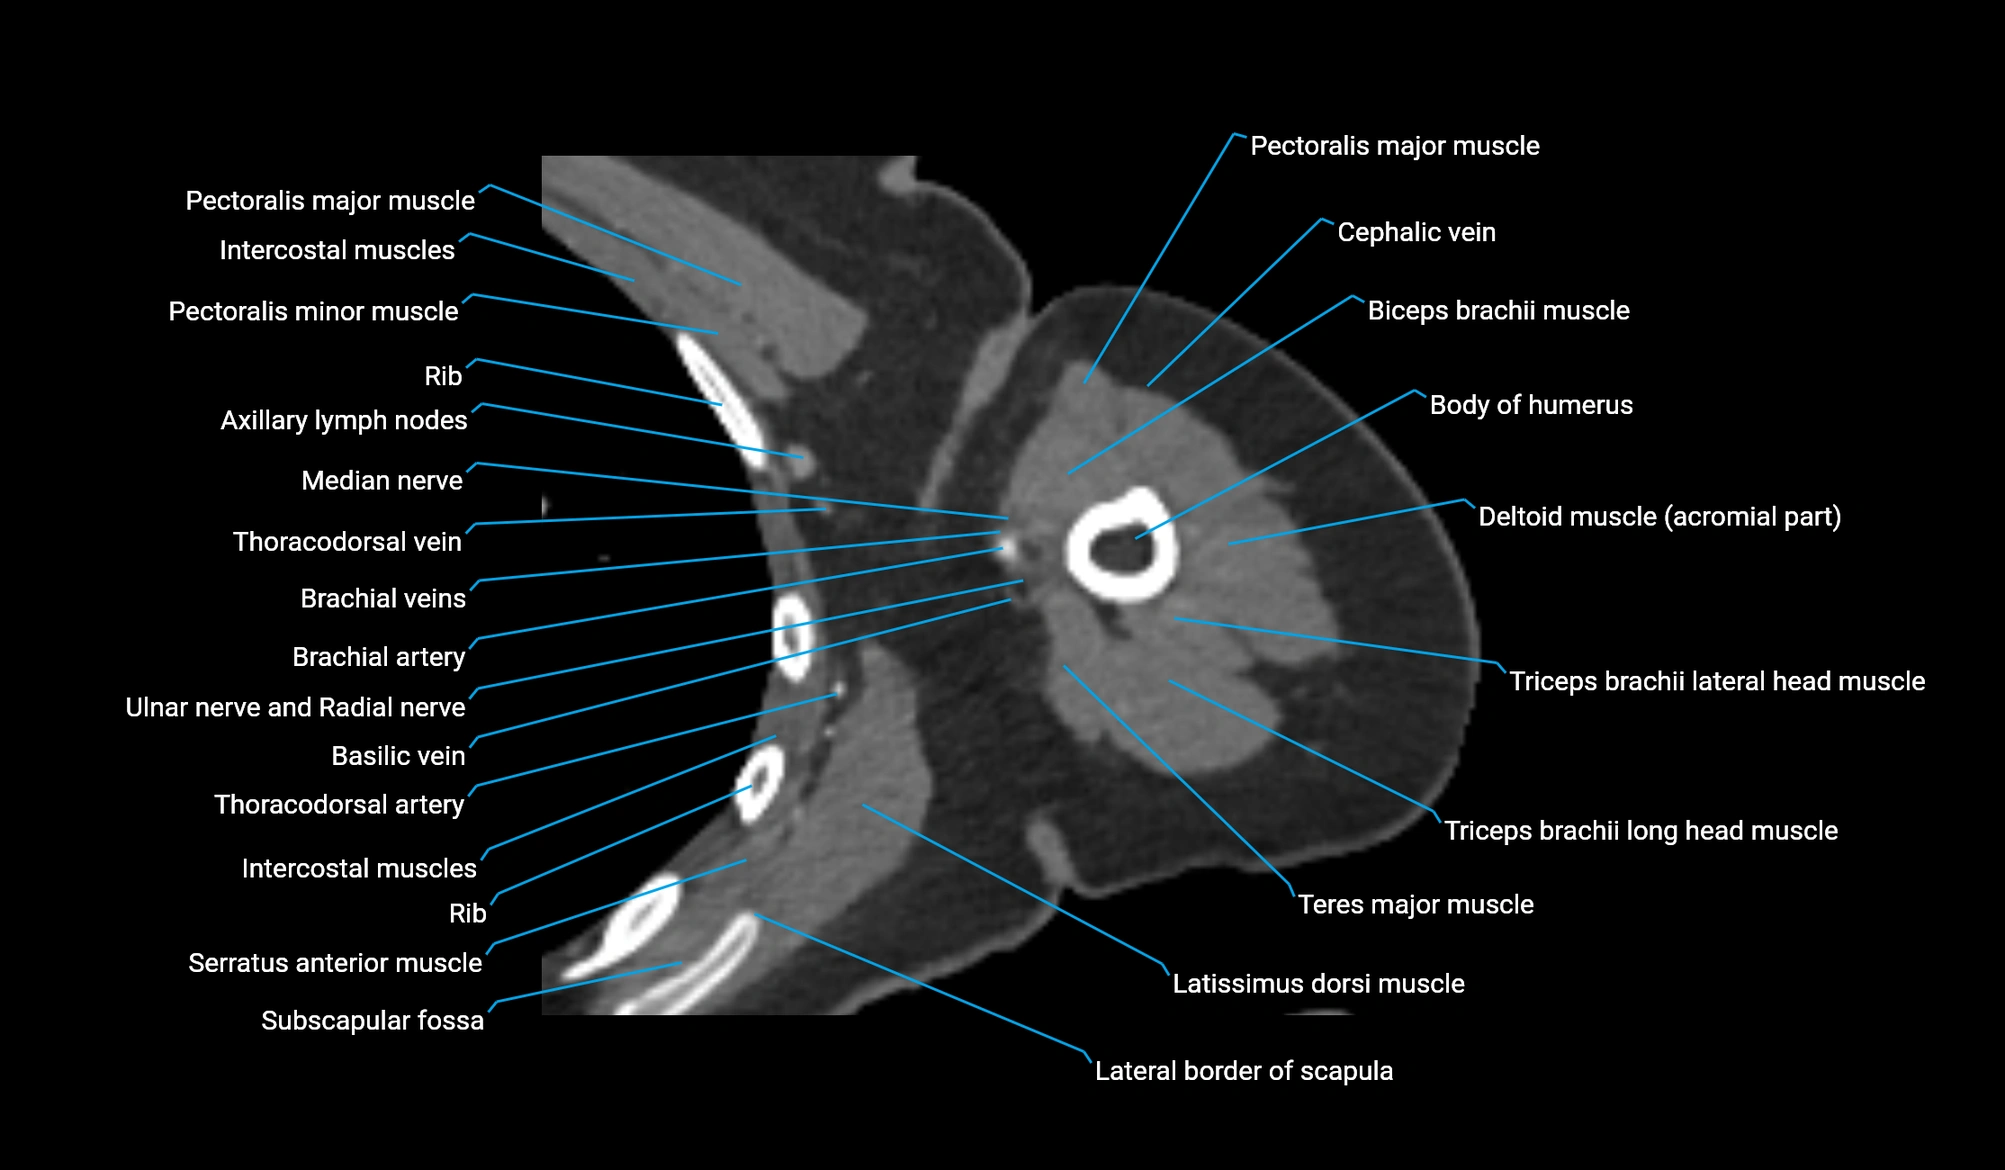

- Axillary lymph nodes

- Basilic vein

- Body of humerus

- Brachial artery

- Cephalic vein

- Lateral border of scapula

- Lateral head of triceps brachii muscle

- Long head of triceps brachii muscle

- Median nerve

- Pectoralis major muscle

- Pectoralis minor muscle

- Subscapular fossa

- Subscapularis muscle

- Teres major muscle

- Thoracodorsal artery

- Ulnar nerve